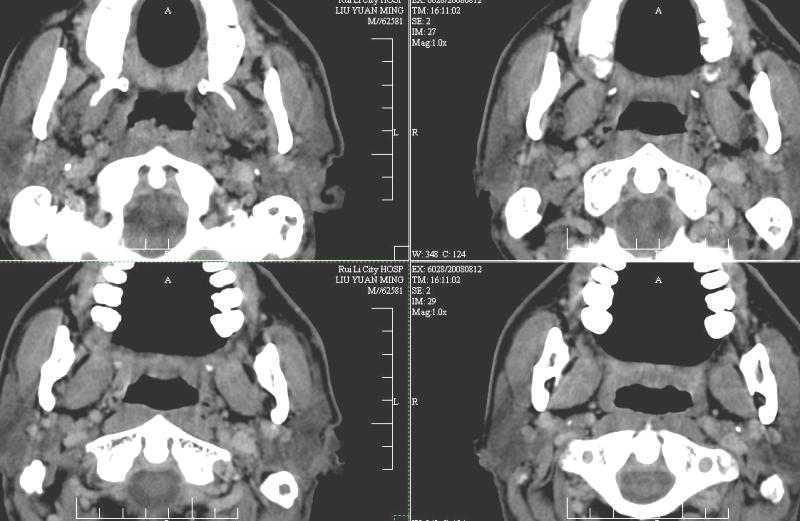

以下是引用ydx_74在2008-8-12 22:09:00的发言:[br]不考虑鼻咽癌。没有淋巴结肿大,没有颅底骨质破坏,咽隐窝、咽鼓管咽口存在,咽旁间隙清楚,平扫ct值34hu,增强动脉期81hu,实质期约85hu,增强幅度达50多,除外增强时机没有掌握好因素,可以考虑鼻咽纤维血管瘤吗?

以下是引用卜一在2008-8-13 8:07:00的发言:[br][br] 鼻咽部新生物,性质待定(不排除鼻咽癌可能);建议行鼻咽镜检查(活检)。 [br]支持!